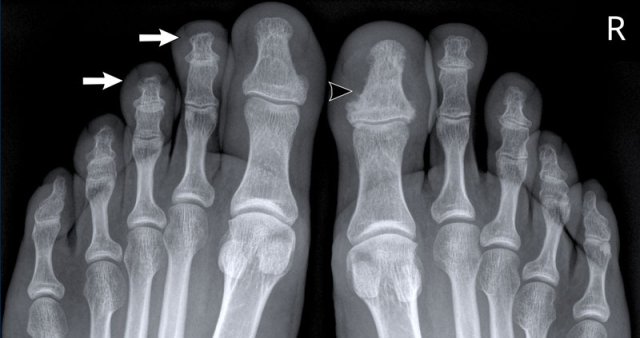

Psoriatic arthritis Psoriatic arthritis

Periostitis in psoriatic arthritis

This is a patient with psoriatic arthritis.

Notice the subtle periostitis of the distal phalanx of dig 1 on the right (arrowhead).

There are small erosions of the tuft of dig 2 and 3 on the left (white arrows).